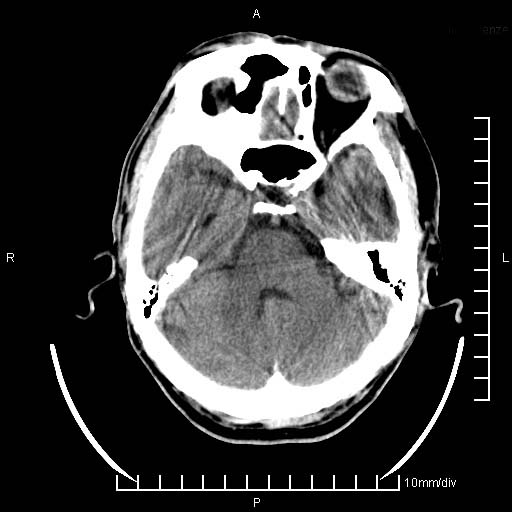

临床以双下肢浮肿,疼痛收治,无明显神经系统症状,既往无梗塞,出血病史。左颞叶见低密度灶,考虑什么?

考虑左侧颞叶脑软化灶。

无强化 无占位 软化灶吧

无强化、 无占位、局部脑沟增宽, 软化灶吧。